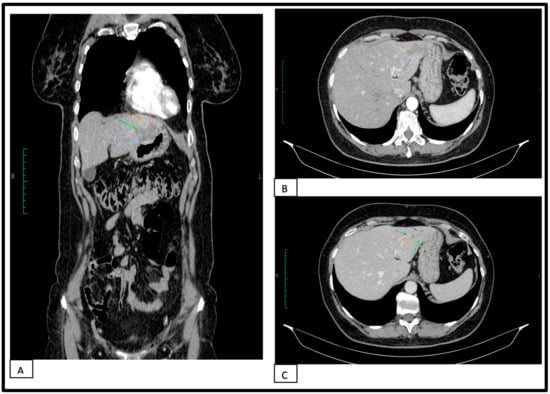

2. Case Report